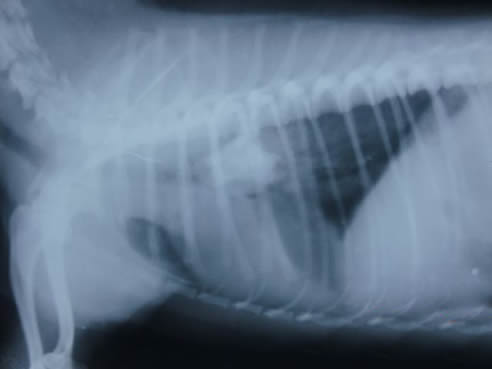

医生帮谢先生做了CT检查,可是仅凭CT片,医生一时也无法判断,只知道谢先生的肺门部位发现了疑似肿块。

医生一边帮助谢先生消炎、祛痰,一边完善相关检查。在使用了支气管镜进入肺门部位查看后,医生惊呆了,发现这个肿块是疑似动物骨头的东西!